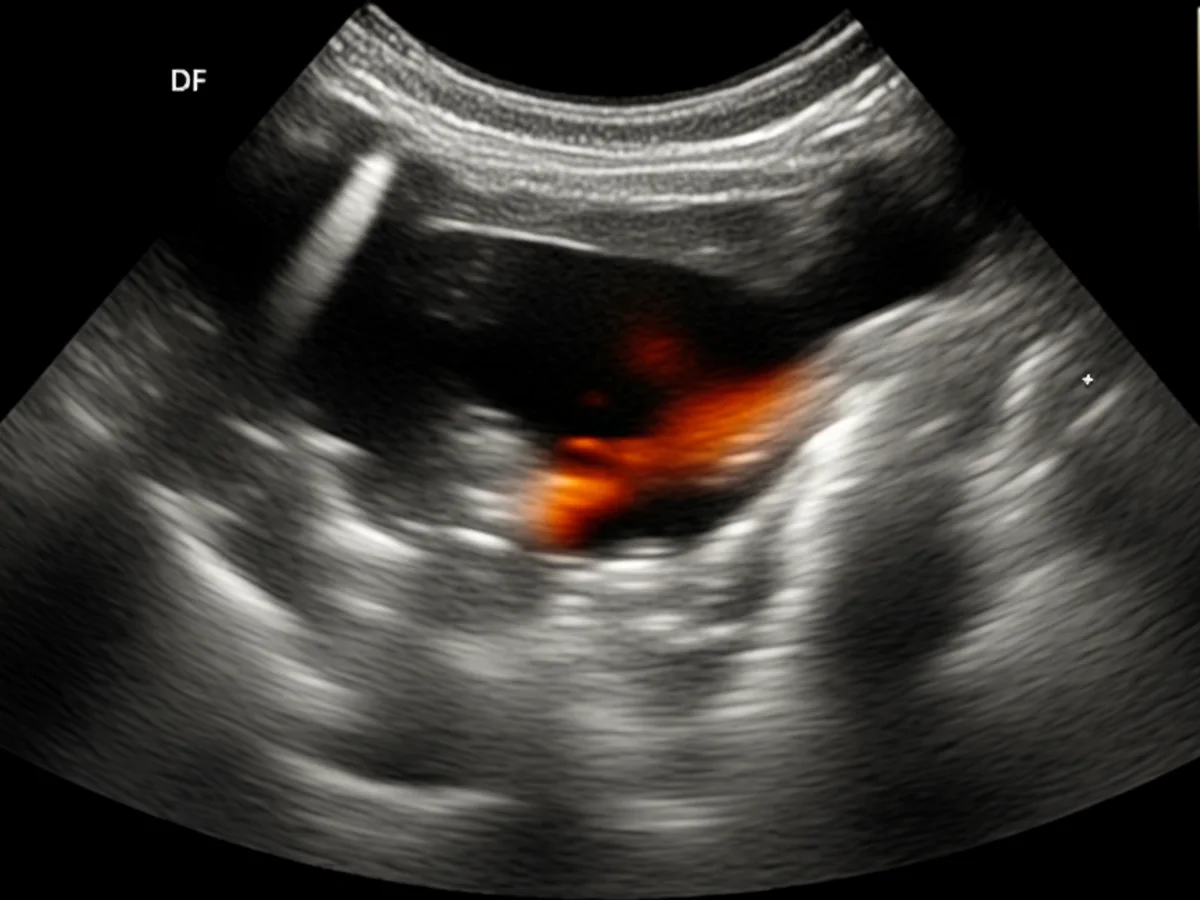

Zur Diagnose eines Bandscheibenvorfalls wird der Tierarzt zunächst eine körperliche Untersuchung durchführen. Dabei wird der Hund auf Schmerzreaktionen und neuromuskuläre Defizite überprüft. Ergänzend dazu können bildgebende Verfahren wie Röntgen, MRT oder CT eingesetzt werden, um den genauen Zustand der Bandscheiben und das Ausmaß des Vorfalls zu bestimmen.